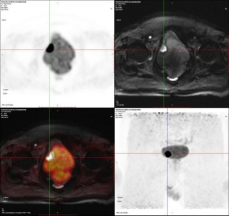

病例1PET/MRI清晰显示膀胱病灶。膀胱右前壁结节,直径约2.0cm,DWI为高信号,相应ADC信号减低,T2抑脂混杂稍高信号,FDG代谢增高。手术病理:(膀胱肿瘤)高级别乳头状尿路上皮癌,局灶可疑微小浸润。